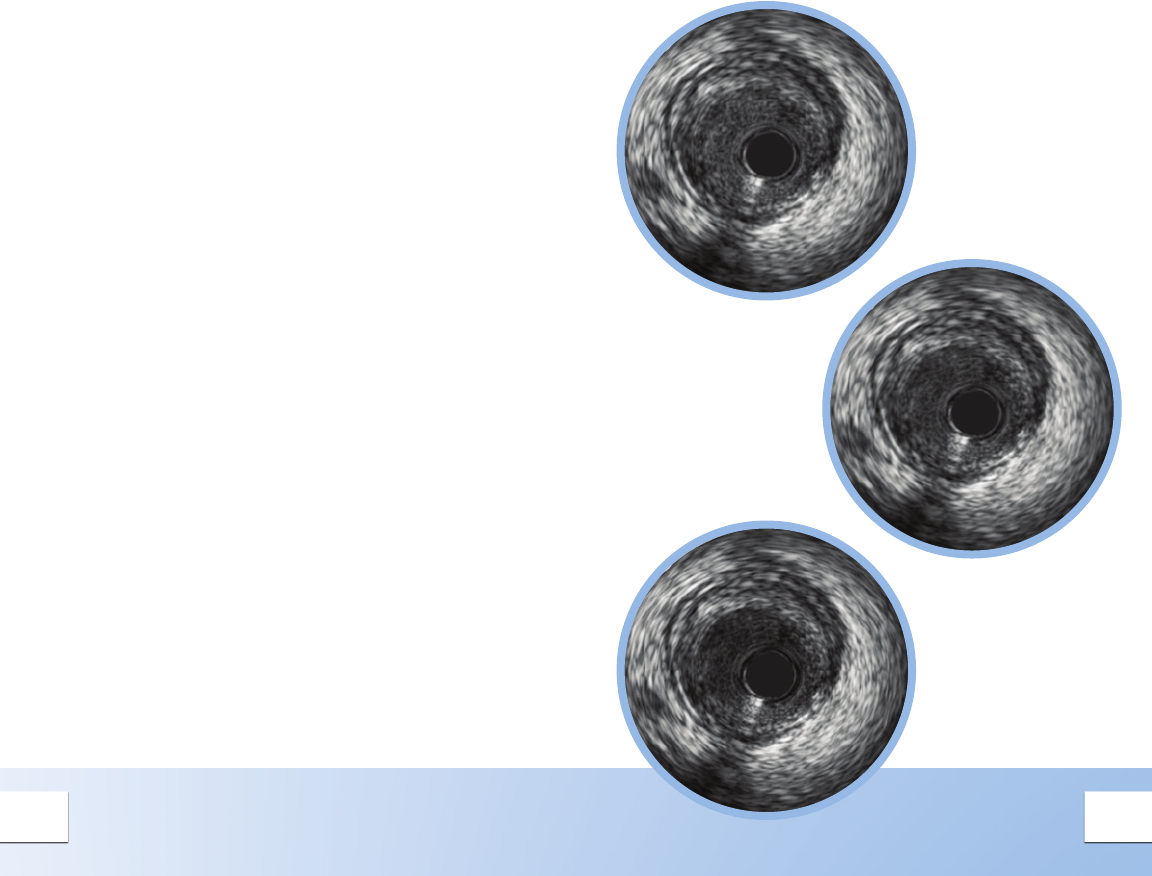

HI-Q™ IMAGING OPTIONS

Hi-Q™ Imaging1 Allows You to

Customize Your Image to Better

Identify Lumen Features

Choose from three high quality2, optimized imaging

modes with different levels of darkness and neness of

blood speckle:

May help differentiate between tissue and blood

along the lumen border

May help identify stent struts, dissection, or other

lumen features

1. Available on all Revolution® catheters when using

v3.3 software or higher.

2. Catheter must be plugged in with Image On;

Selection accessible via the Adjust Image Menu.

Hi-Q OFF

Imaging

equivalent to

systems with

software versions

prior to v.3.3.

Hi-Q LEVEL 2

Imaging with an

even darker and

ner blood speckle

appearance than in

the Level 1 mode.

Hi-Q LEVEL 1

Imaging with a darker

and ner blood

speckle appearance

than in the Off mode.

Level is also the default

mode1 for new systems.